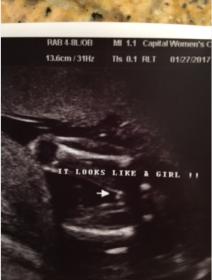

Anatomy Scan Gender Prediction - doctor 97 percent sure

Yesterday we had our anatomy scan at 19 weeks, our baby was being very stubborn and wouldn't uncross their legs most of the scan. The doctor believes she got the right picture to determine gender and said she is 97% sure. We had a gender reveal last night and are over the moon about the baby being a GIRL. I had a feeling it was a boy so i was in complete shock. But now that i keep looking at the picture i am very nervous it could actually be a boy and she was wrong. I don't want to start buying to much stuff if she is wrong. If anyone could please give me their thoughts it would be greatly appreciated!!!! Attachment 34691